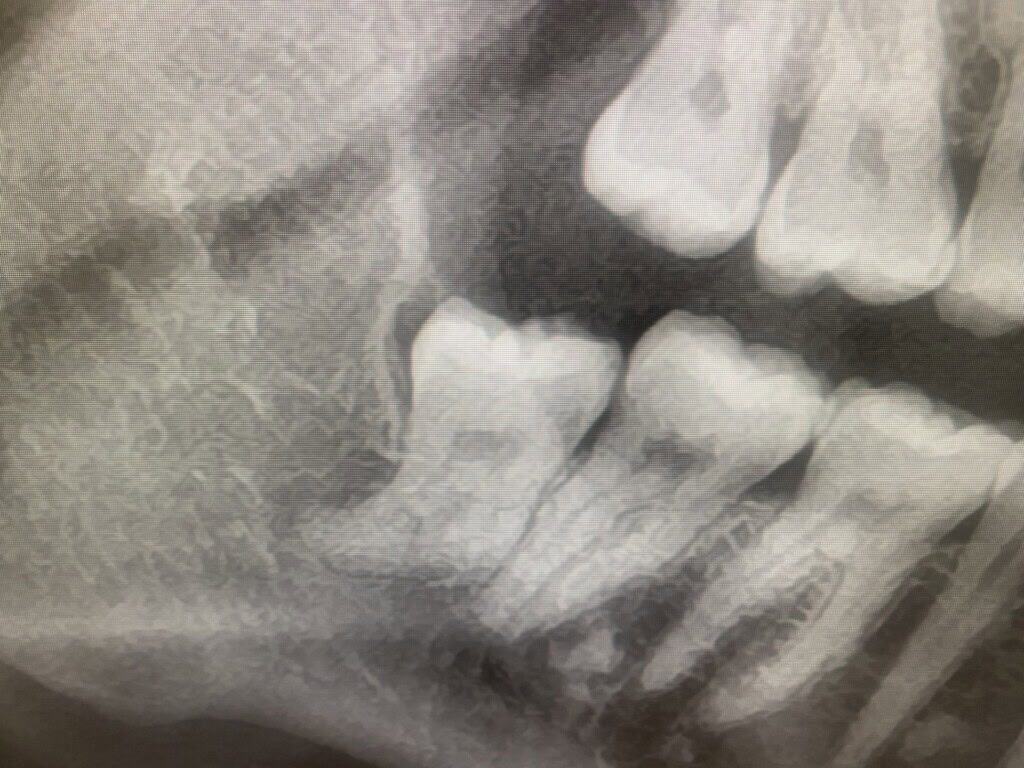

Anatomy is complex, risk needs to be reduced... Trust our specialist Consultant Oral Surgeon to take out your complicated teeth....